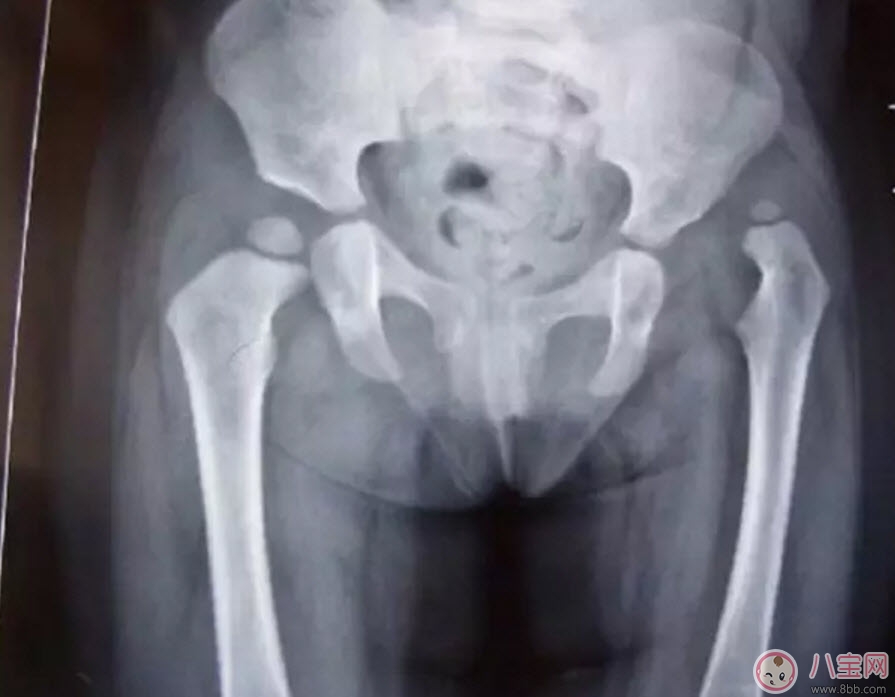

這是一個(gè)左側(cè)髖關(guān)節(jié)脫位的孩子的X光片。從這張片子上我們可以看到,孩子右側(cè)的髖關(guān)節(jié)是正常的,股骨頭和關(guān)節(jié)盂在一個(gè)水平位置上,但左側(cè)的股骨頭就完全離開(kāi)了髖關(guān)節(jié)盂,跑到髖關(guān)節(jié)的上方去了,對(duì)于左側(cè)這種情況,我們就稱之為髖關(guān)節(jié)脫位。一般這種脫位都是先天的,或是孩子很小時(shí)候出現(xiàn)的,所以除了關(guān)節(jié)有脫位外,左側(cè)的股骨頭、股骨干、髖臼發(fā)育的也不正常,明顯比正常的一側(cè)要小。